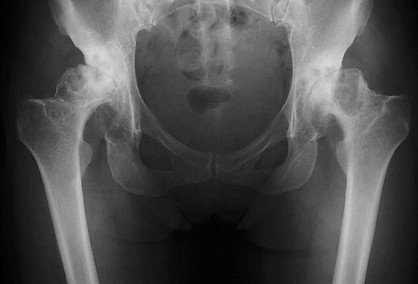

40代女性

両側末期形成不全性股関節症 両股関節をエクセターステム、骨セメントを使用し、再建した。術後14年経過したが、摩耗、弛み、骨粗鬆を認めず元気に働いている。

手術前